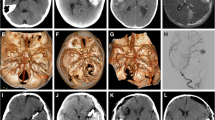

A non-contrast computed tomography (NCCT) of the head is the first investigation in a child with suspected intracranial bleeding. If the NCCT or clinical findings suggest SAH, additional imaging in the form of CT angiogram (CTA) or magnetic resonance angiogram (MRA) of the circle of Willis can be done (Fig. 22.1). The sensitivity of both CTA and MRA to pick aneurysms more than 5 mm in size approaches 100%. With recent advances, the sensitivity to pick even small aneurysms approximates 98–100% [16]. The potential advantage of MRA over CTA is that it does not require iodinated contrast use and limits the exposure of harmful ionizing radiation in young children. Digital subtraction angiography (DSA), while invasive, is the gold standard for the diagnosis of cerebral aneurysms and gives detailed information about the exact site, size, configuration, and neck of the aneurysm, which is important for making treatment decisions (Fig. 22.2).

In a 4-year-old child, axial NCCT head showed (a) well-defined hyperdense lesion (thick white arrow), s/o bleed with perilesional hypodensity (edema) in right temporal lobe with thin SDH in right temporal lobe convexity (thin white arrow). Axial T2 MRI showed (b) well-defined flow void in right distal M1 MCA (thick white arrow) with gliotic changes in the right temporal lobe (thin white arrow). Phase contrast MRI showed (c) intense enhancement within the aneurysm (thick white arrow). Time of flight MRA showed (d) a well-defined aneurysm in right distal M1 MCA (thick white arrow)

Digital subtraction angiography right ICA AP run showed (a) a well-defined lobulated aneurysm in right distal M1 MCA (thick arrow) with paucity of cortical vessels in right MCA territory (thin arrow). DSA 3D images (b–d) showed lobulated aneurysm in right distal M1 MCA, directed antero-supero-laterally (thick white arrow)